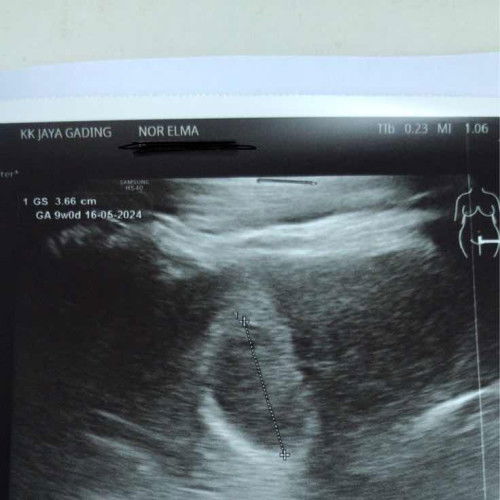

Scan nampak kantung

Hi nak tanya . Kalau gambar macam ni, kantung ke ?? Dan baby ada dalam tu ?? Sy sebenarnya trauma sbb mse 1st pregnancy dulu scan2 tk nmpak apa2. Then gugur. Harap kalini gambar ni memberi sejuta bahagia lah untuk saya . Doktor ckp dah ada baby, kaki tgan kepala smua ad. Tp sy tk nmpak. Hehe. Saya dah 10w. Mse scan ni 9w. #ingintahu #pleasehelp #firstmom